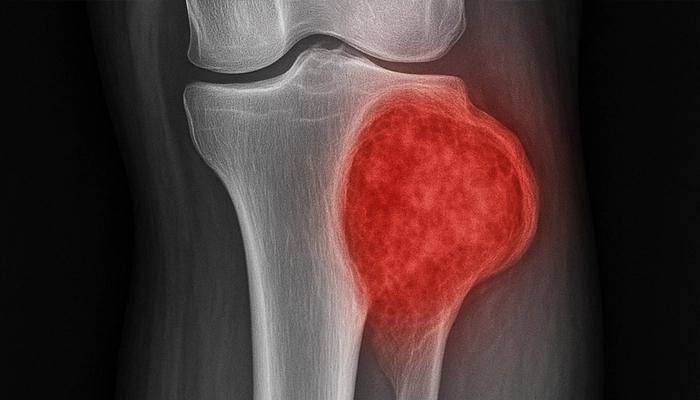

U tế bào khổng lồ (Giant Cell Tumor - GCT) là một loại khối u xương có đặc tính giáp biên, thường xuất hiện ở các đầu xương dài gần khớp. Khối u này hình thành do sự tăng sinh bất thường của các tế bào đơn nhân, kích thích các tế bào khổng lồ đa nhân (hủy cốt bào) hoạt động mạnh, gây tiêu xương và phá hủy cấu trúc khớp.

U tế bào khổng lồ (GCT) chiếm khoảng 5% các loại u xương nguyên phát và khoảng 20% các loại u xương lành tính. Về mặt giải phẫu, khối u này thường "ưu ái" vị trí vùng quanh khớp, đặc biệt là đầu dưới xương đùi, đầu trên xương chày (vùng gối) và đầu dưới xương quay (vùng cổ tay).

Khác với các khối u lành tính thông thường vốn phát triển chậm và có ranh giới rõ ràng, u tế bào khổng lồ có xu hướng xâm lấn mạnh tại chỗ. Nó không chỉ làm mỏng lớp vỏ xương mà còn có thể phá vỡ vỏ xương để xâm nhập vào phần mềm xung quanh hoặc lấn vào trong ổ khớp. Dù được xếp vào nhóm lành tính, một tỷ lệ nhỏ (khoảng 1-3%) khối u này có thể di căn lên phổi, mặc dù các tế bào di căn vẫn giữ hình thái của tế bào lành tính. Điều này khiến giới y khoa coi GCT là một khối u "hung hãn" trong nhóm các tổn thương xương không ung thư.

Bác sĩ thường sử dụng hệ thống phân loại Campanacci dựa trên hình ảnh X-quang để đánh giá mức độ xâm lấn:

Giai đoạn I (Thể tiềm tàng): Khối u nằm gọn trong xương, ranh giới rõ ràng với lớp vỏ xương nguyên vẹn.

Giai đoạn II (Thể hoạt động): Khối u mở rộng làm mỏng vỏ xương nhưng chưa phá vỡ nó. Đây là giai đoạn thường gặp nhất trên lâm sàng.

Giai đoạn III (Thể hung hãn): Khối u phá vỡ vỏ xương, xâm lấn vào phần mềm hoặc vào trong ổ khớp. Nguy cơ tái phát sau phẫu thuật ở giai đoạn này rất cao.